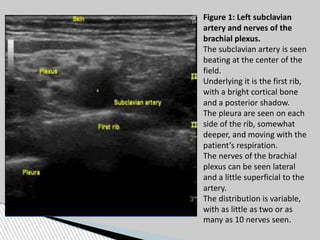

Figure 1: Left subclavian

artery and nerves of the

brachial plexus.

The subclavian artery is seen

beating at the center of the

field.

Underlying it is the first rib,

with a bright cortical bone

and a posterior shadow.

The pleura are seen on each

side of the rib, somewhat

deeper, and moving with the

patient’s respiration.

The nerves of the brachial

plexus can be seen lateral

and a little superficial to the

artery.

The distribution is variable,

with as little as two or as

many as 10 nerves seen.